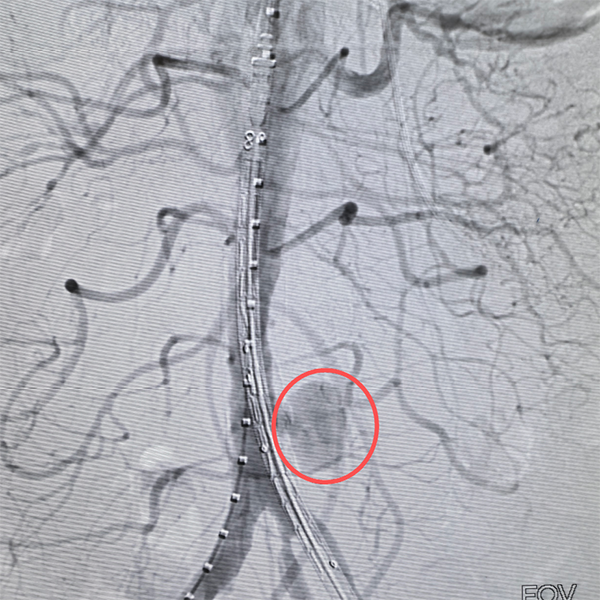

凌晨时分,导管室灯火通明。介入科喻四龙主任团队紧急上阵,在DSA下行腹主动脉造影+腹主动脉覆膜支架腔内隔绝术。随着支架精准释放,破裂口被成功封堵,孙大伯转危为安。

术前